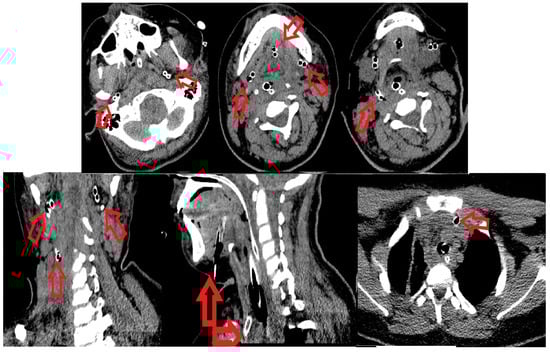

During the 7th day in ICU, the postoperative wounds were reviewed. Local evolution was favorable, and fascial necrosis and pathological secretions were absent. Granulation tissue is present in the wound. These aspects led us to the decision of finally closing the wound (wound secondary sutures) and of suppressing the remaining drain tube located in the anterior mediastinum (Figure 3).

Figure 3. (a) Absence of the local fascial necrosis and pathological secretions and (b) wound secondary sutures and the last drain tube located in the anterior mediastinum that was removed.